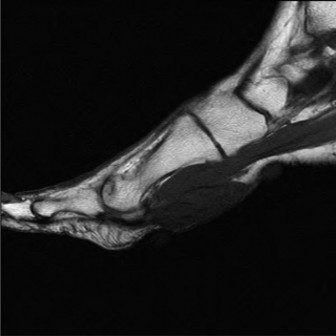

• Magnetic Resonance Imaging (MRI): The gold standard for soft tissue evaluation.

• Precisely characterizes masses (cystic vs. solid, vascularity).

• Assesses PTT integrity (tendinosis, partial tears, full ruptures).

• Evaluates inflammatory changes (bone marrow edema, tenosynovitis).

• Defines relationship of mass to neurovascular structures.

• Image (This image, potentially an MRI, could illustrate PTT pathology or an accessory navicular.)